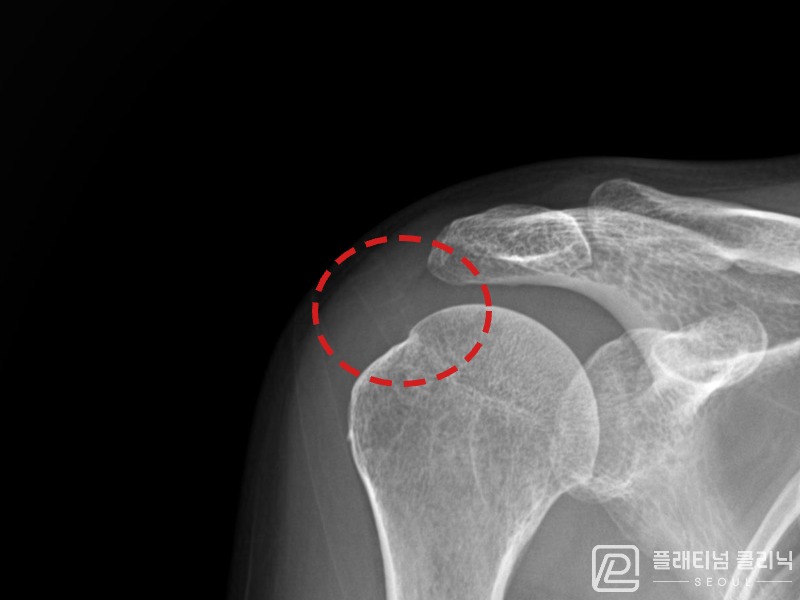

[촬영시기:21.08.30~21.09.09]

[석회분쇄흡입술] 우측 어깨 통증으로 밤잠을 못 이루고 팔을 올리기 어려워진 30대 여성 환자로, X-ray에서 우측 극상근건 내 석회 침착이 확인되어 석회분쇄흡입술을 시행하였습니다.